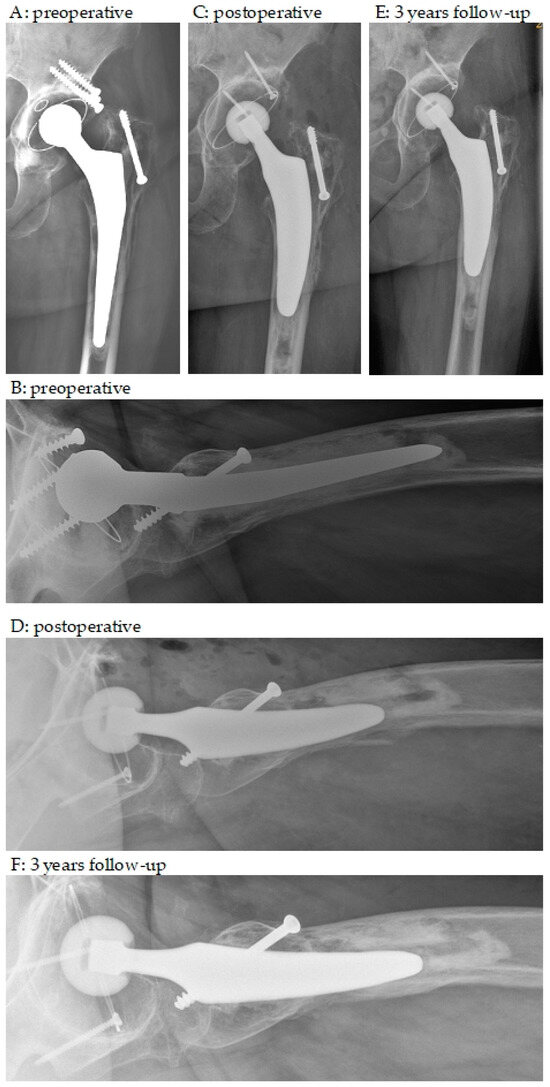

3.2. Radiographic Outcomes